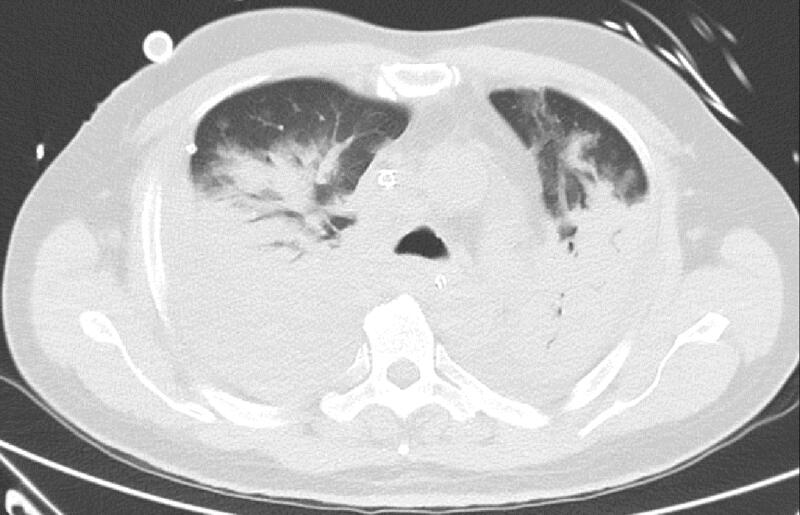

Ảnh chụp cắt lớp cho thấy phổi của ông Tol chứa đầy chất lỏng do bị nhiễm COVID-19.